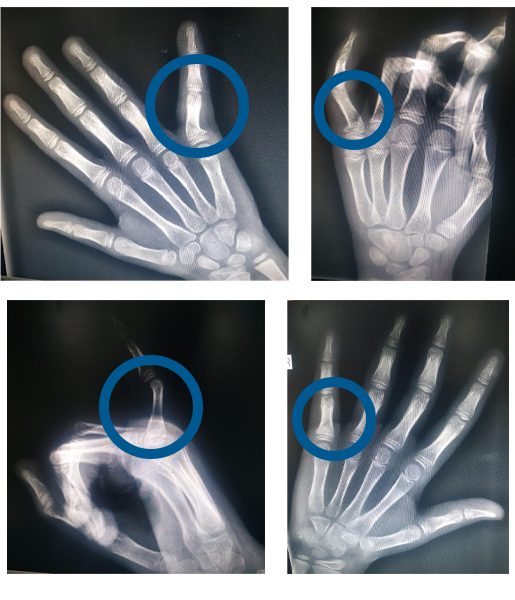

Case - 4

Close reduction of displaced finger fracture in a 6 year old girl

Before

Ap & Oblique X rays showing fracture and displacement at base of left little finger

Post reduction images showing complete correction of the deformity

After